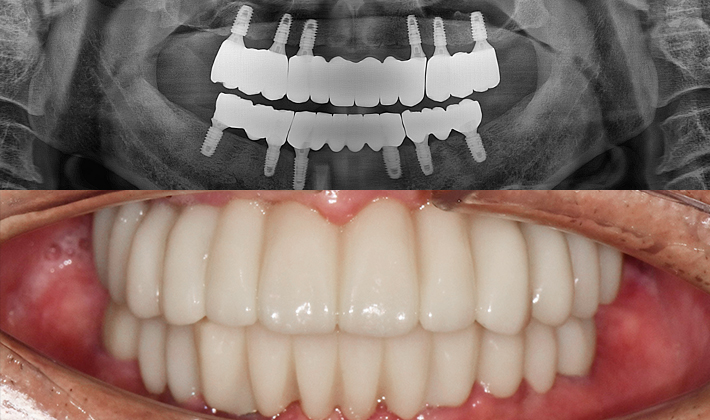

치과가 무서워 10년 동안 미뤄온 임플란트 수술 그 결과는?

2026.01.21